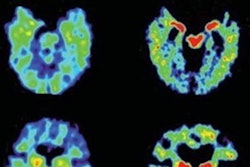

The patents are associated with F-18 flornaptitril (also known as F-18 FDDNP), a biomarker for the detection, development, and progression of Alzheimer's disease, as well as chronic traumatic encephalopathy and other neurodegenerative diseases.